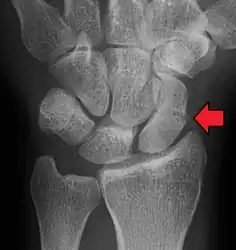

A subtle scaphoid fracture

A more obvious scaphoid fracture on a scaphoid view X ray

Radiolucency around a 12 days old scaphoid fracture that was initially barely visible.[11]

Fracture of the tubercle of the scaphoid bone of the wrist